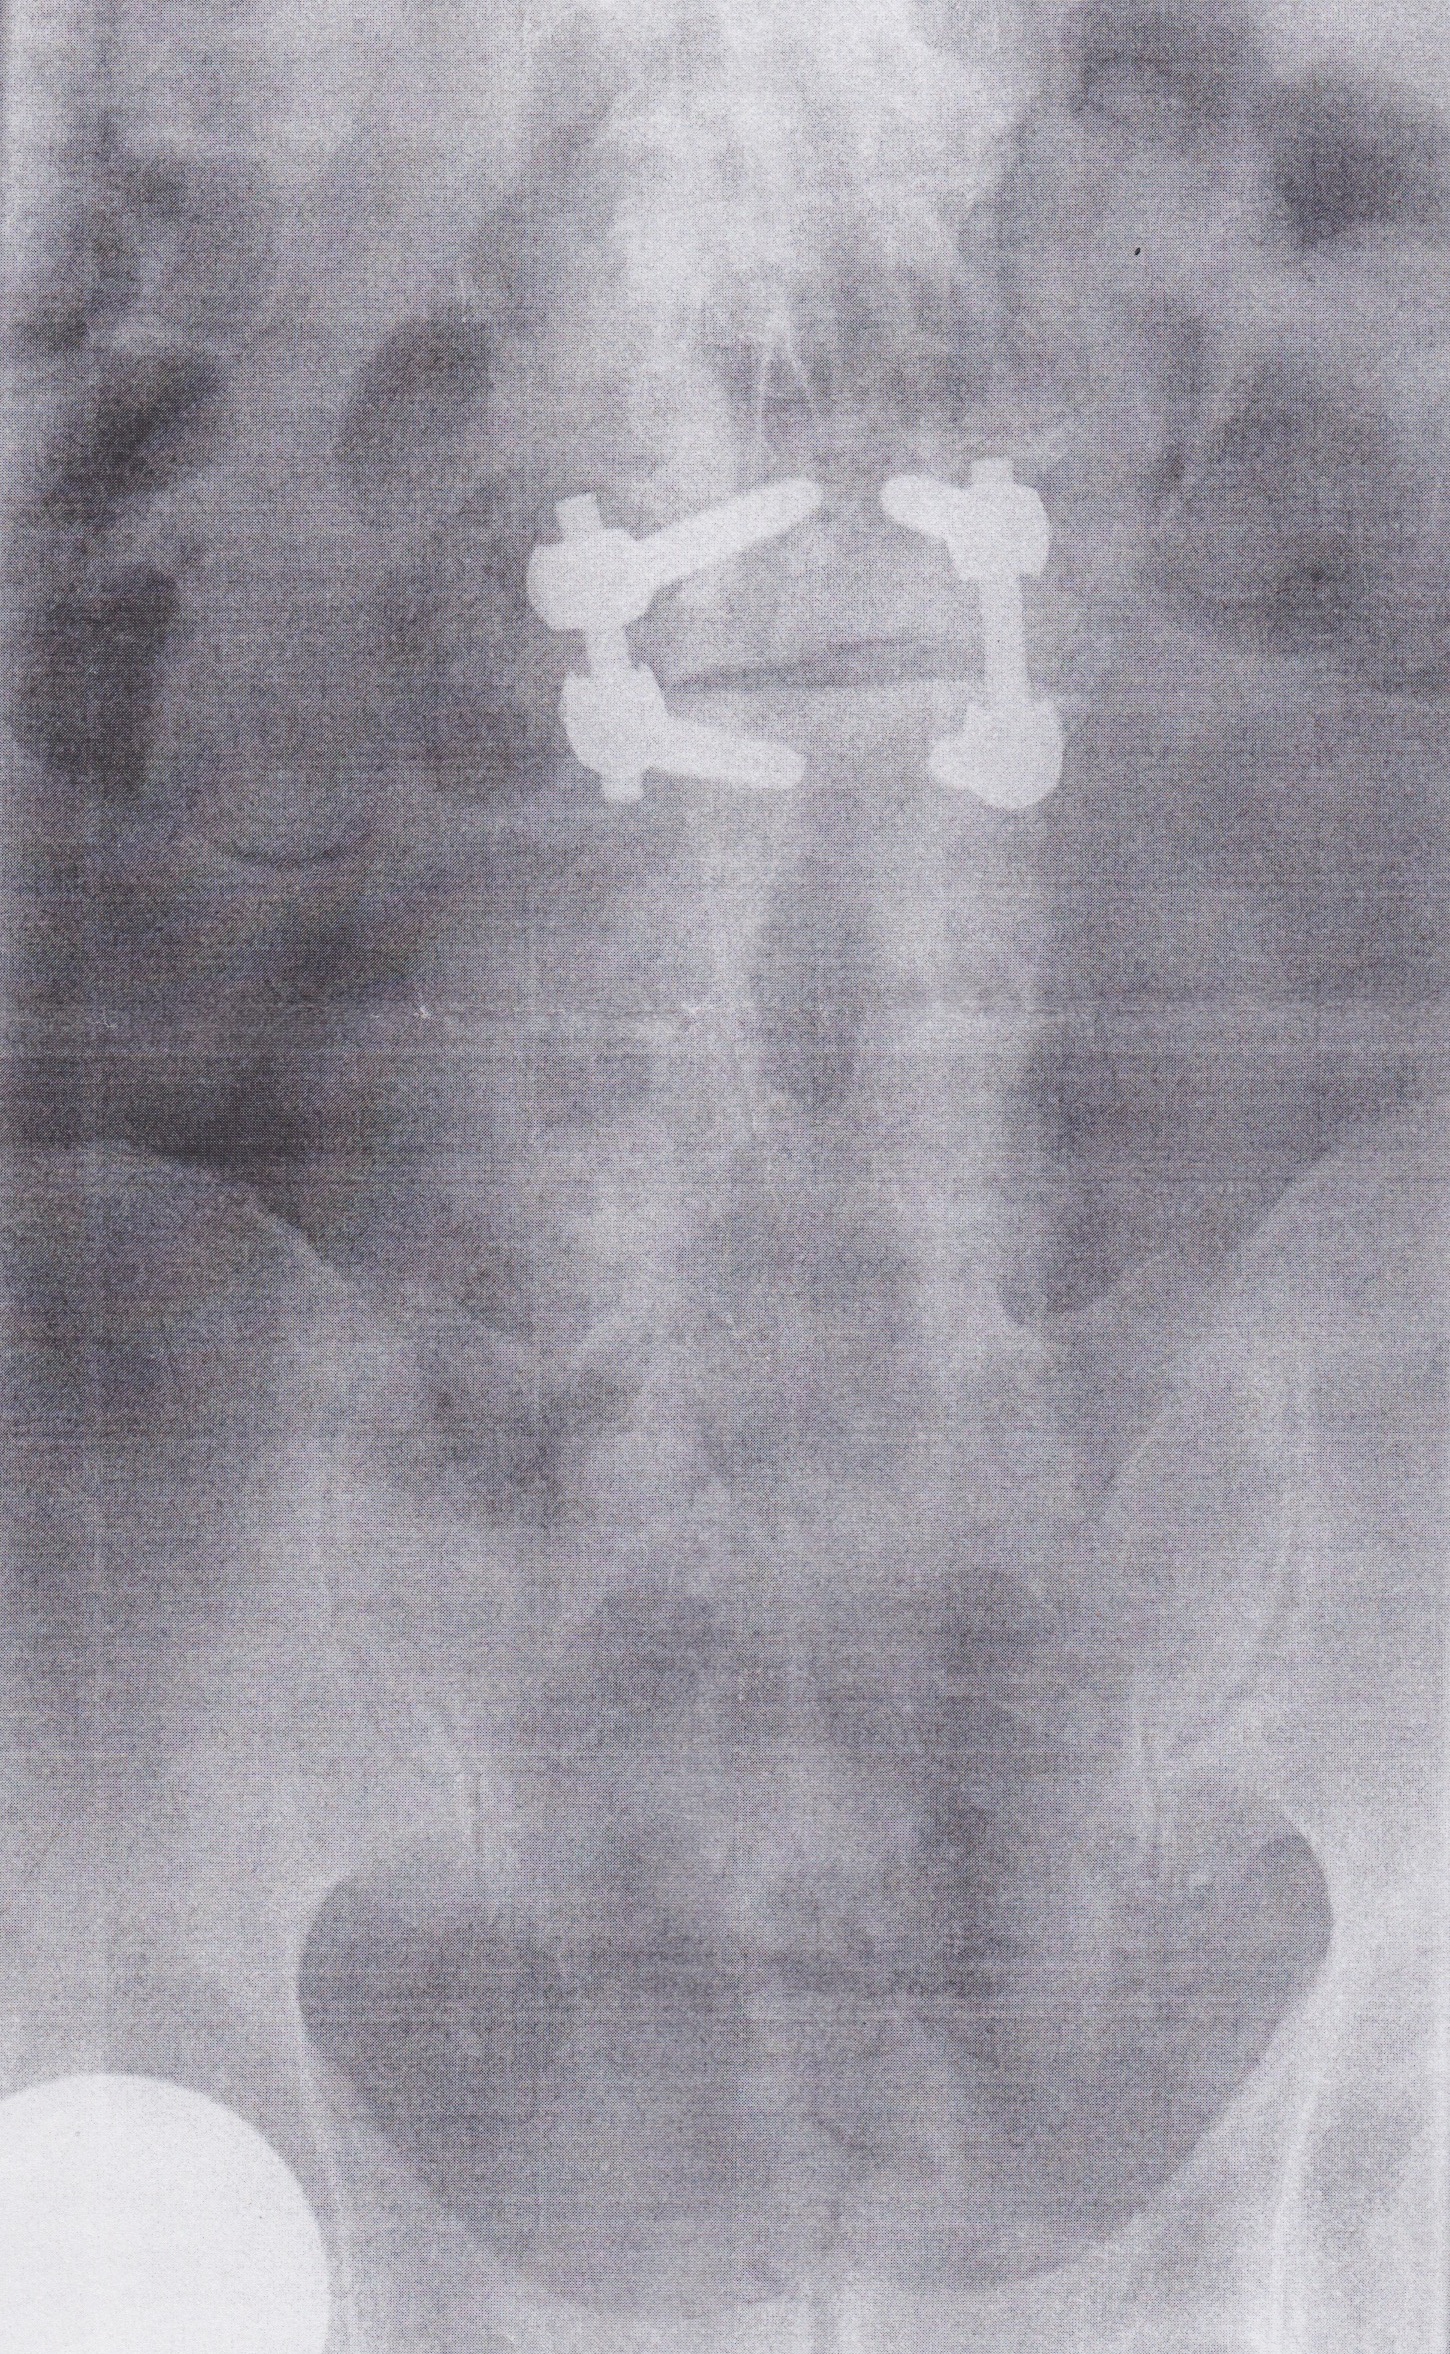

Since 2008, I’d had three levels of vertebrae bolted together. Here are two more views of the original job:

In January, 2013: Bob removed the old fusion hardware and installed bolts and screws at the next level up. You can espy the ball of my still-functional seven-year old bionic hip-joint at lower left. |